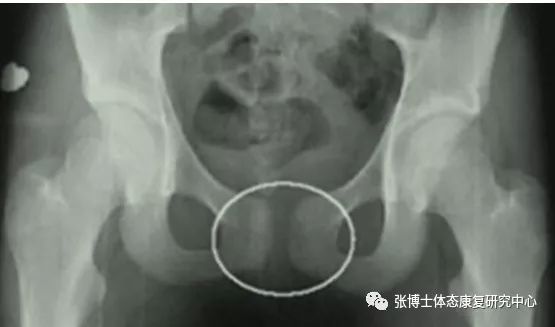

3、影像学检查:正常人耻骨间隙为4~6mm,孕期可增宽2~3mm。影像学X线片见耻骨联合间距离明显增宽,一般认为耻骨联合间隙超过10mm可确诊。